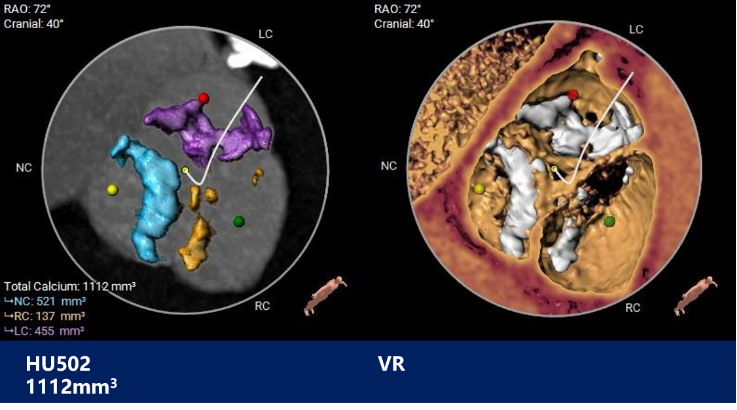

主动脉根部测量

CT特点:三叶式主动脉瓣,重度钙化,钙化分布欠均匀,无冠窦和左窦钙化较重,右窦较轻,主要分布在瓣叶边缘及血管壁附着缘,瓣叶增生肥厚,未见明显融合;左右冠高度可,冠脉切线位瓣叶长度<冠脉开口到瓣叶根部附着缘距离。